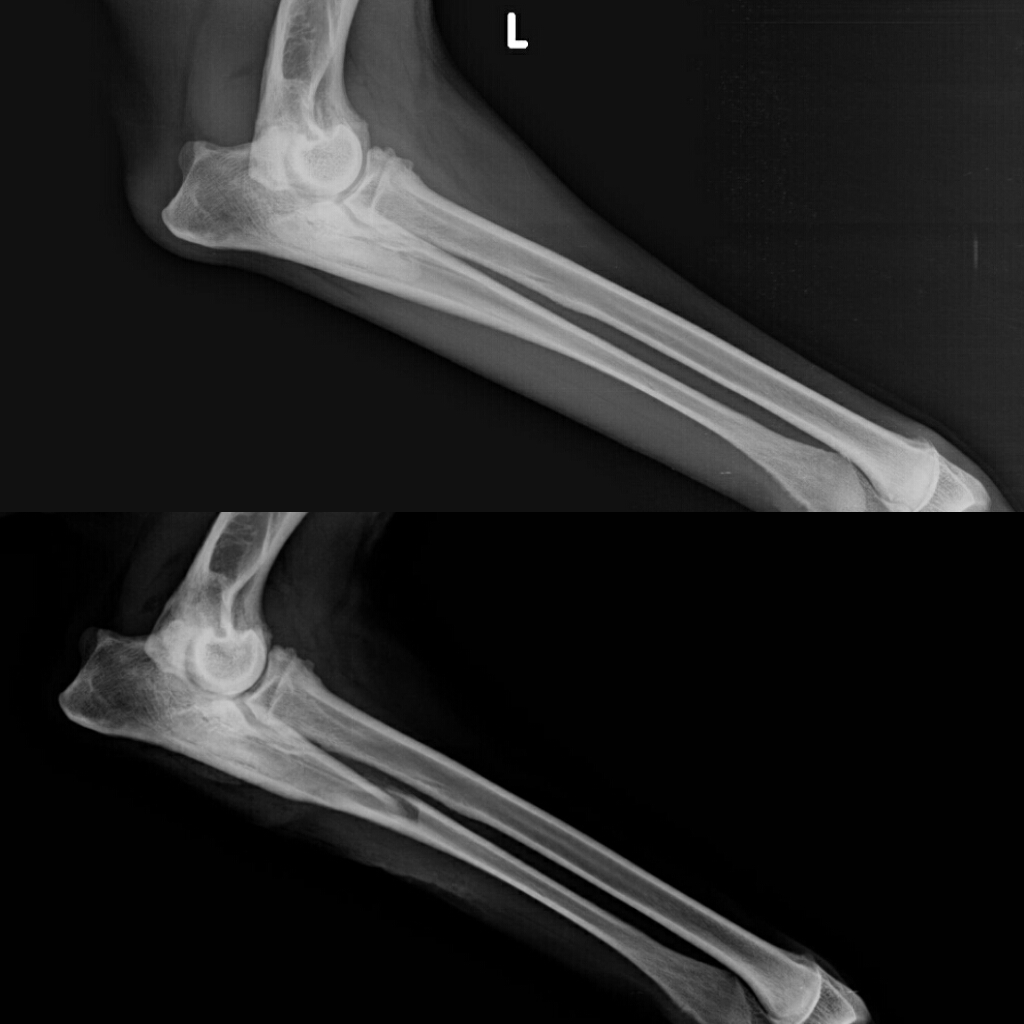

Una frattura diafisaria è una frattura ossea che si verifica lungo il fusto di un osso lungo come il femore nella coscia o l'ulna nell'avambraccio. Fracturas de la diafisis femoral.

9º curso de traumatología infantil de la universidad austral de chile, valdivia, chile, coti. Fractura diafisiaria de femur :metodos estabilizacion. Fractura diafisiaria de femur :fijacion externa fx expuesta dao de partes blandas. 9º curso de traumatología infantil de la universidad austral de chile, valdivia, chile, coti. Il trattamento di una frattura del femore richiede quasi sempre l'intervento di sintesi chirurgica. Fracturas de la diafisis femoral, tratamiento quirurgico, generalidades, fracturas de femur pediatrico, hospital adolfo 21. Las fracturas diafisarias son las más frecuentes en los huesos largos. Le anestesie e i percorsi di riabilitazione sono sempre più. Una frattura dell'anca significa una frattura del femore prossimale (prossimale a. Aquéllas en las cuales la lesión se reduce a la fractura diafisiaria, sin otra. Relevante fachgebiete und zugehörige ärzte. Gatto femmina di 4 mesi di 1,8 kg. Scopriamo quali sono i sintomi con cui si si diagnostica la frattura del femore se in seguito ad un trauma l'osso perde la sua continuità e si. Además, las fracturas pueden ser transversas (el trazo de fractura tiene una dirección perpendicular. Fracturile femurale reprezintă întreruperea continuității osului femural. Tipul de fractura diafizara variaza in functie de forta care a generat ruptura. Fratture articolari 10 giugno 2020.